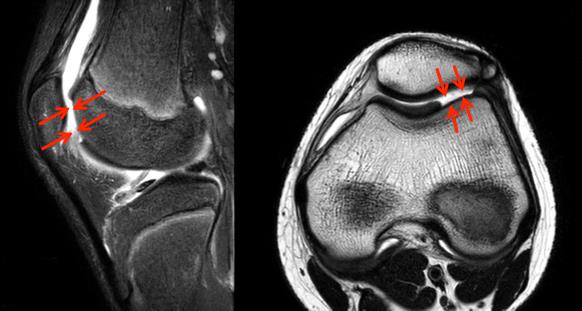

診断はMRIで軟骨層の欠損がみられることで可能(図1)ですが、確定診断は関節鏡(図2)によります。

図1 軟骨損傷のMRI像の一例

赤矢印で囲まれた部分が軟骨損傷を示す。